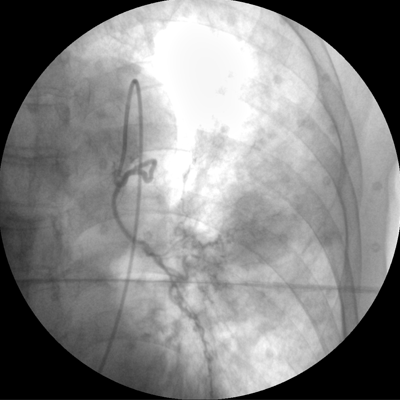

專(zhuān)業(yè)的圖像處理系統(tǒng),為您提供高分辨率、高灰階圖像。